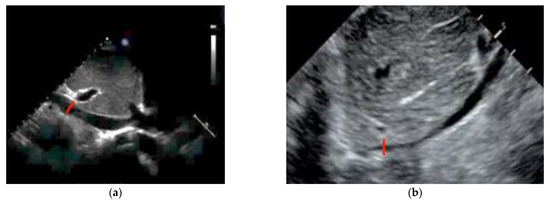

3.4.4. Pulmonary Embolism